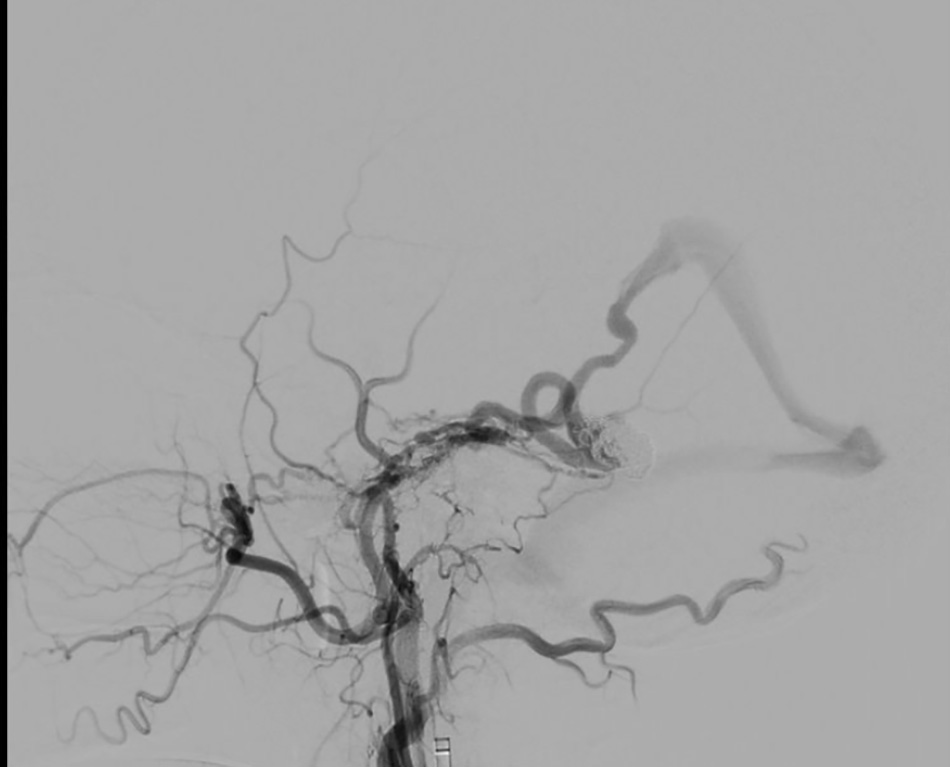

The image shows that the aneurysm has been completely occluded with coils.

After just a few hours, the patient stabilized, with no further nausea and a reduced headache. MRI scans in the following days confirmed that the brain haemorrhage had not progressed and was gradually resolving. Mr F. was discharged after two weeks of monitoring.